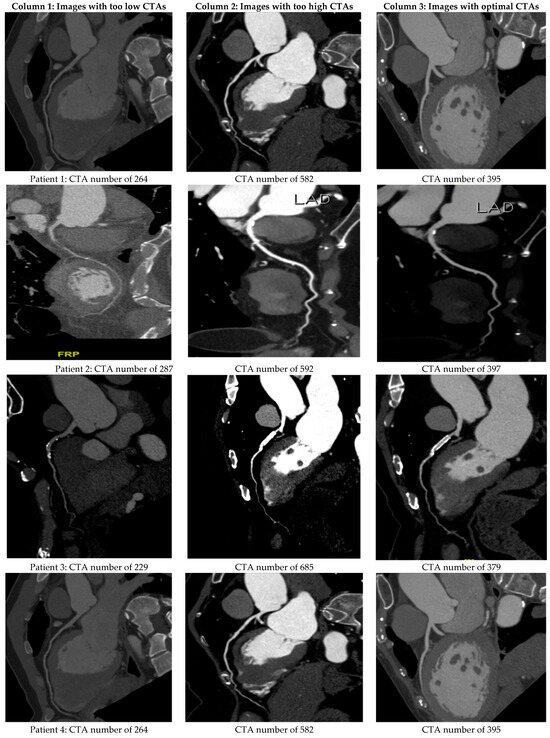

Figure 5 shows the CT images obtained with optimal, too-low, and too-high CTA numbers of LA for six of the sixty-five patients in the testified group. The optimal imaging quality provided a suitable diagnosis and reduced any misreading or misinterpretation of imaging in clinical treatment.

Figure 5.

The actual CTA imaging quality for six patients in the testified group of sixty-five. Columns 1, 2, and 3 correspond to the derived CTA numbers that are too low, too high, or optimal, respectively.